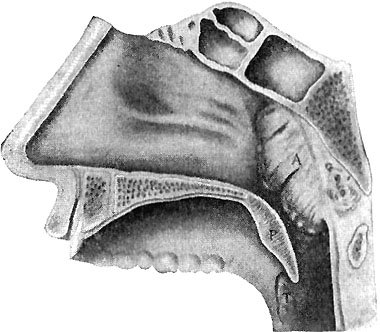

256 Adenoids

257 Mouth-Breathers

Nowadays, in the best dairies, it is required that the barns or sheds in which cows are milked shall have tight walls and roofs and good flooring; that the walls and roofs shall be kept white-washed; and the floor be cleaned and washed be{35}fore each milking, so that no germs from dust or manure can float into the milk. Then the cows are kept in a clean pasture, or dry, graveled yard, instead of a muddy barnyard; and are either brushed, or washed down with a hose before each milking, so that no dust or dirt will fall from them into the milk. The men who are to milk wash their hands thoroughly with soap and water, and put on clean white canvas or cotton overalls, jackets, and caps. As soon as the milk has been drawn into the pails, it is carried into the milk-room and cooled down to a temperature of about forty-two degrees—that is, about ten degrees above freezing point. This is to prevent the growth of such few germs as may have got into it, in spite of all the care that has been taken. Then the milk is drawn into bottles; and the bottles are tightly capped by a water-proof pasteboard disc, or cover, which is not removed until the milk is brought into the house and poured into the glass, or cup, for use.